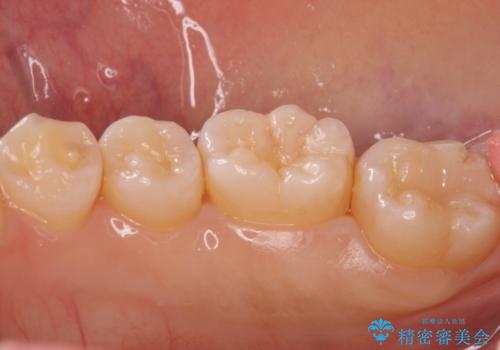

奥歯の深い黒ずみ セラミックインレーでの治療

変色しない材料をご希望されたためセラミックインレーでの治療となりました。

- 右下7 セラミックインレー 77,000円費用は治療当時の料金となります

樹脂は変色していきますがセラミックは変色しない材料であるため、長く使いたい方にお勧めです。